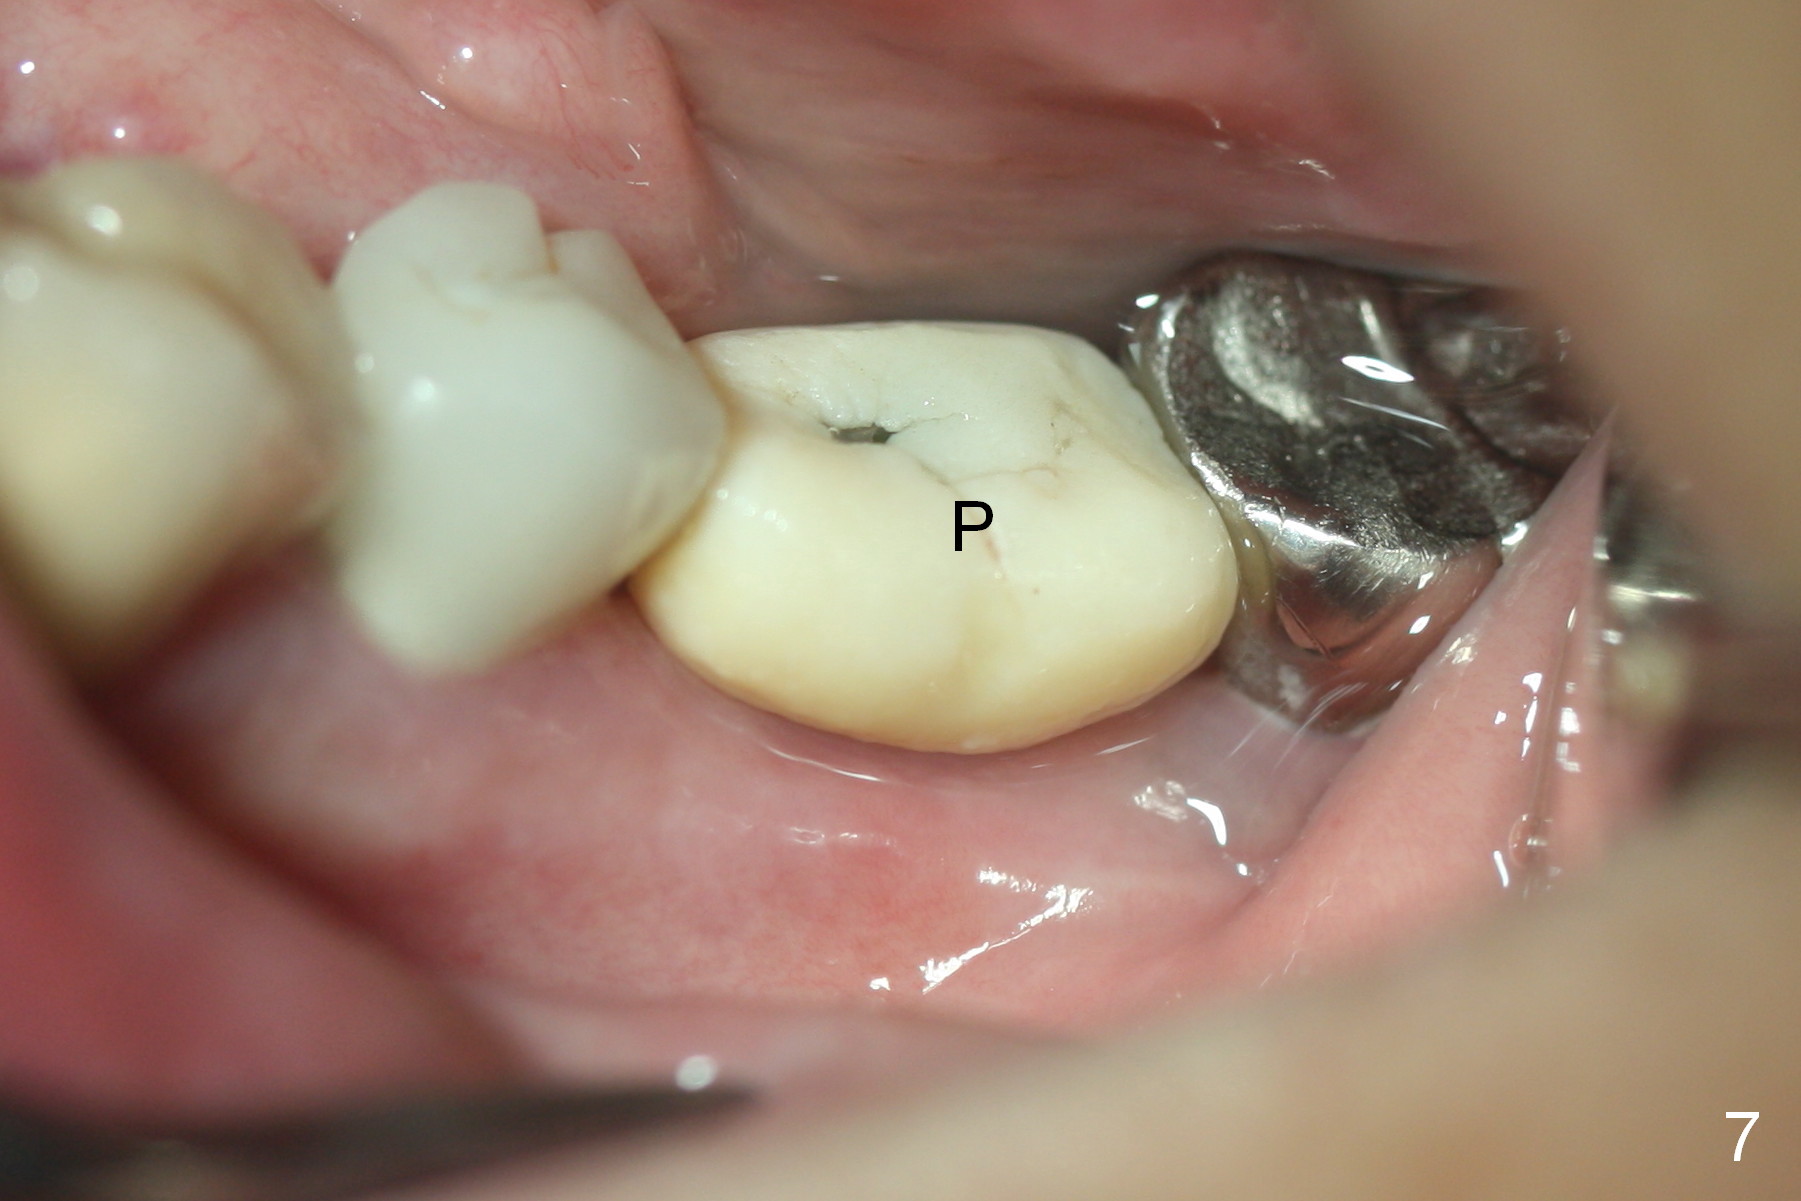

Two months post impression (4 months postop), the patient returns for cementation. The provisional is perforated again in the occlusal surface (Fig.7 P). When the provisional is removed, a shallow trough forms around the abutment (Fig.8*). The bony defect appears to be repaired 1 year 9 months post cementation (Fig.9).